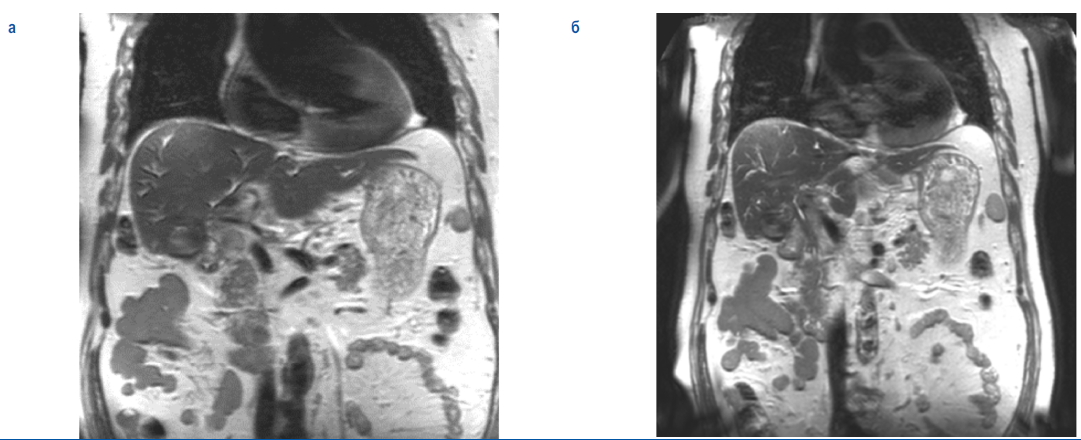

По данным магнино-резонансной томографии (МРТ) ОБП – формальная МР-картина опухоли Клатскина с распространением на пузырный проток и желчный пузырь. Метастатическое поражение лимфатических узлов брыжейки и печеночно-двенадцатиперстной связки (рис. 2, 3).

Рис. 2. Изображение магнитно-резонансной томографии – опухоль ворот печени.

Fig. 2. MRI scan – hilar cholangiocarcinoma.

Рис. 3. Изображение магнитно-резонансной томографии – опухоль ворот печени.

Fig. 3. MRI scan – hilar cholangiocarcinoma.